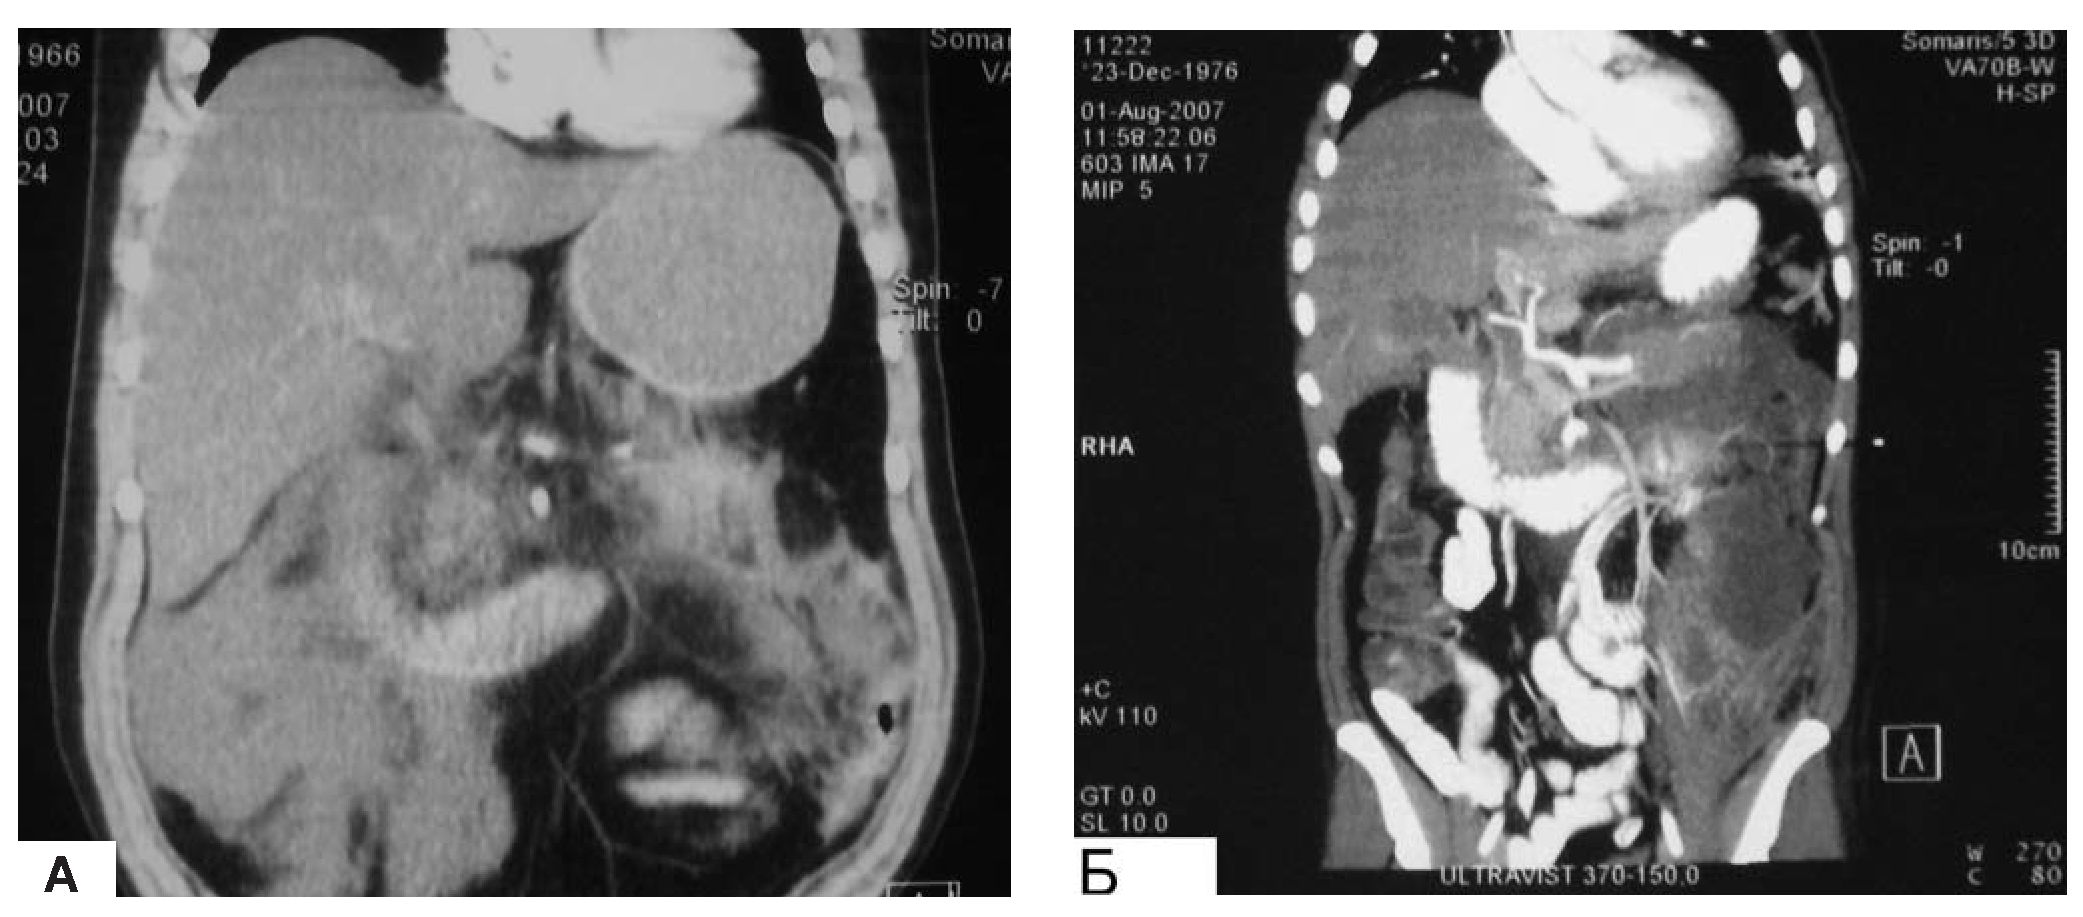

В наших случаях использование систем интегральной оценки тяжести состояния и прогноза (Ranson, Apache-II) показало их невысокую значимость и достоверность (менее 50%) в клинической практике. В большинстве случаев тяжесть состояния пациента, рассчитанная с помощью шкалы Ranson и Apache-II, не совпадала с его объективным статусом. Наиболее достоверными факторами прогнозирования течения ПН оказались: активность в динамике заболевания С-реактивного белка, нейтрофилов, прокальциотонина, данные УЗИ и КТ брюшной полости, выделяемая микрофлора. С целью оценки динамики процесса в брюшной полости и забрюшинном пространстве УЗИ выполняли через каждые 2-3 суток, а КТ не реже 1 раза в неделю (рис. 7).

Рис. 7. Компьютерная томограмма при субтотальном инфицированном ПН, забрюшинной флегмоной справа (А) и слева [Б].